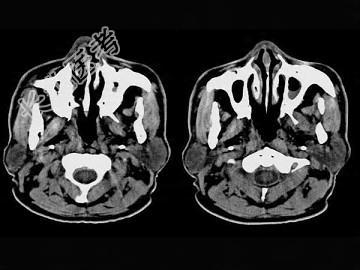

- 单项选择题男,61岁, 流鼻血三天。如图所示最可能的诊断为 ( )

A、鼻咽淋巴滤泡增生

B、鼻咽腺样体增生

C、鼻咽纤维血管瘤

D、小唾液腺瘤

E、鼻咽部息肉